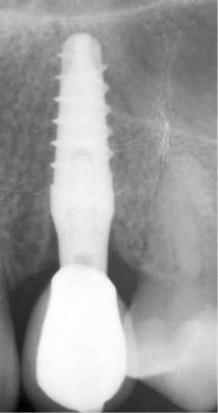

La morfologia convergente del collo Prama permette di recuperare la porzione di tessuto molle che con un impianto transmucoso tradizionale verrebbe occupata dal titanio del collo implantare. La convergenza di Prama fa sì che i volumi intorno alla porzione coronale dell’impianto vengano invece riempiti di coagulo e di importanti fattori di ricrescita, che si trasformano in tessuti molli spessi e funzionali.

L'ispessimento della gengiva che circonda il collo Prama rappresenta un beneficio indiscusso, soprattutto nei pazienti con biotipo più sottile, nei quali questo innovativo impianto apporta un ispessimento dei tessuti molli senza ricorrere a terapie rigenerative.

La stabilizzazione del connettivo, resa possibile dalla morfologia convergente e dalla microrigatura UTM, fa sì che tutto ciò che vi è al di sotto rimanga protetto e isolato da potenziali attacchi batterici, e che quindi l’osso si mantenga preservato in maniera efficace e a lungo, come ampiamente dimostrato dalla clinica.